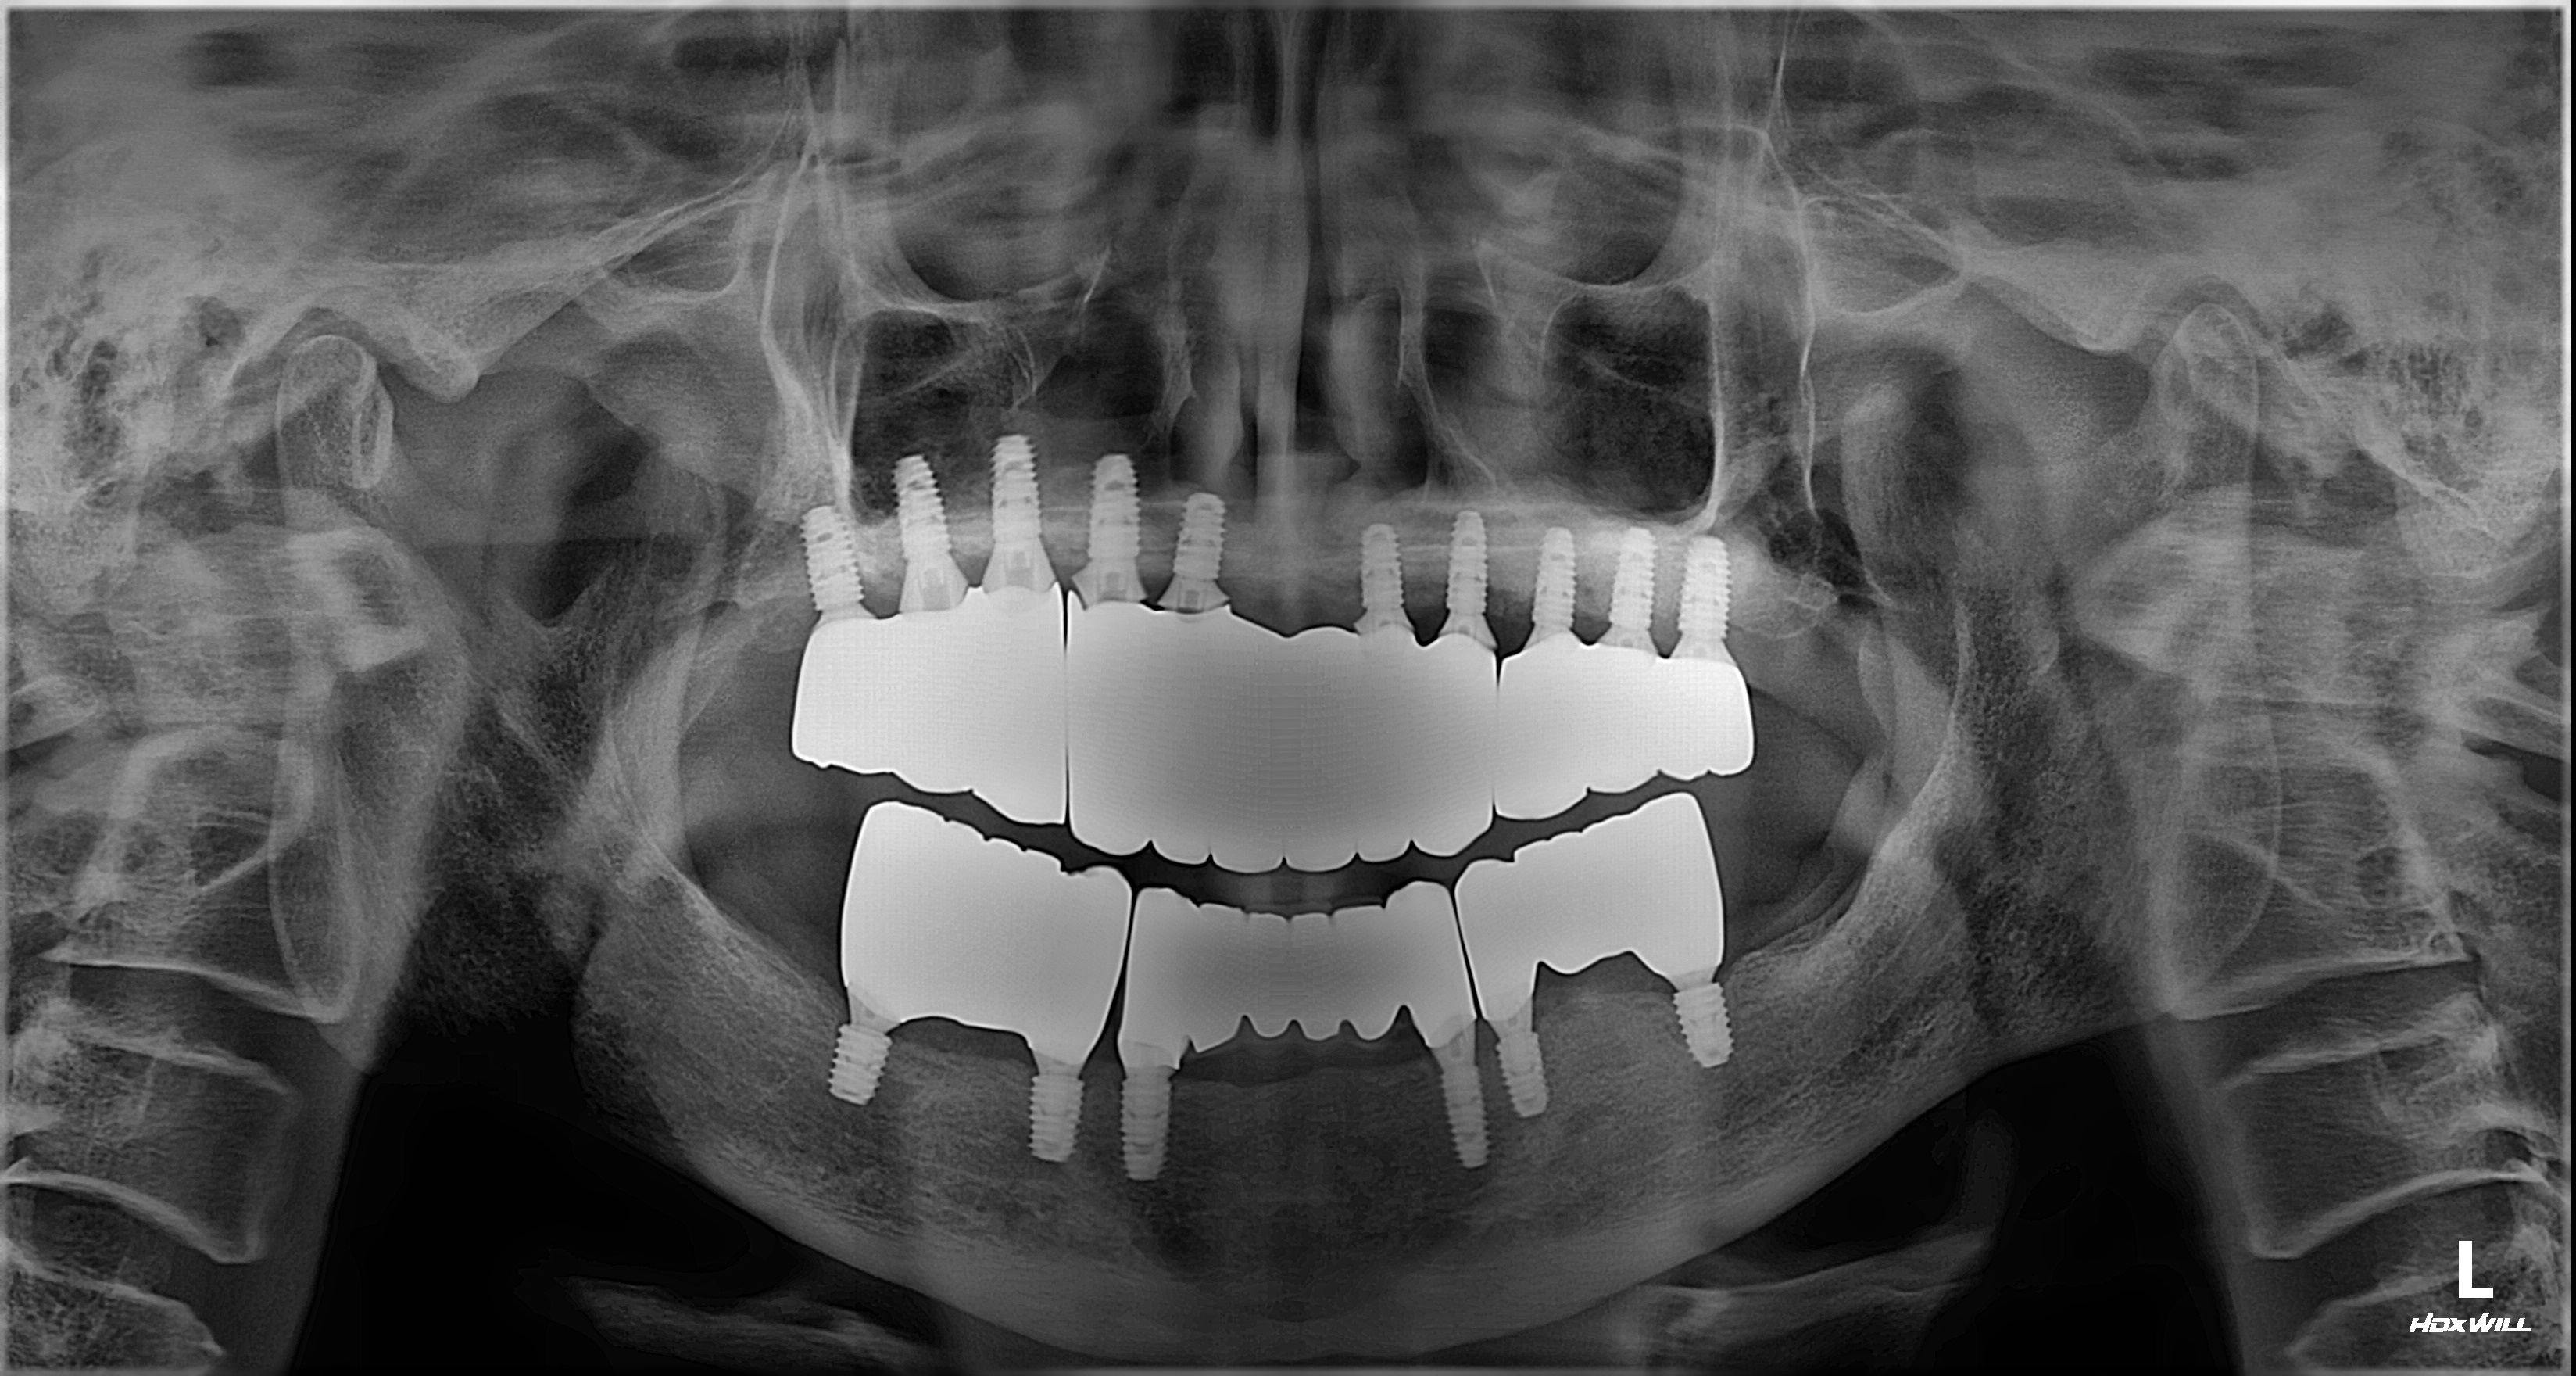

촬영일시: 2024.05.03

[ 치료기간: 2024년 05월 03일 ~2025년 03월 14일 ] ※ 365서울앞선치과의원의 모든 컬럼은 각 진료과 의료진이 직접 작성합니다. 365서울앞선치과의원 임상 케이스 게시물은 환자분께 의학적으로 정확하고 상세한 정보를 드리기 위해 각 진료과 의료진이 직접 작성하며, 모든 증례 사진은 본원 의료진이 직접 시술한 증례를 촬영한 것으로, 의료법 제23조, 제56조에 의거하며 환자분의 동의를 얻어 포스팅에 사용하였습니다. 또한 해당 케이스는 본 환자분의 치료 결과이며, 환자 상태에 따라 치료의 결과는 달라질 수 있습니다. |